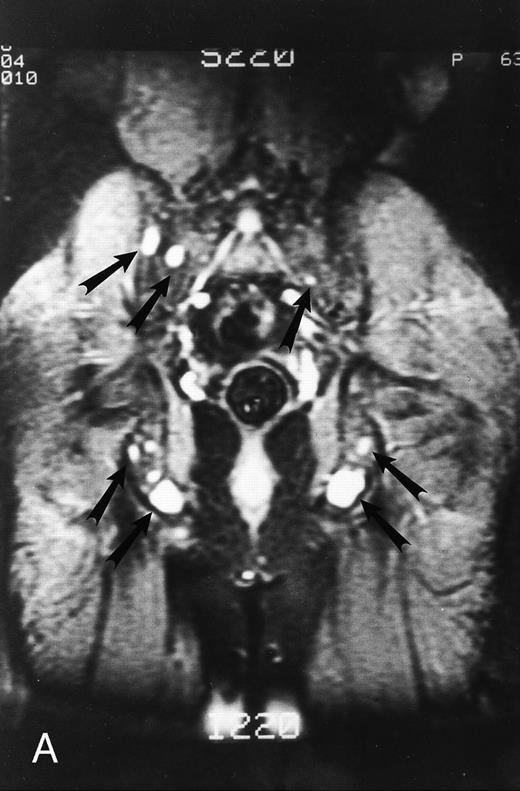

STIR images before and after bone marrow transplantation in a middle-aged man with multiple myeloma and a focal pattern of bone marrow involvement. Pretransplant STIR (2500/20/160, TR/TE/TI) coronal MR image of the pelvis (A) shows multiple bright foci (arrows) in the pelvic bones. Posttransplant STIR (2500/20/160, TR/TE/TI) image (B) shows a decrease in the size and number of the lesions. Courtesy of E.J.C. Angtuaco, MD (University of Arkansas for Medical Sciences, Little Rock, AR).